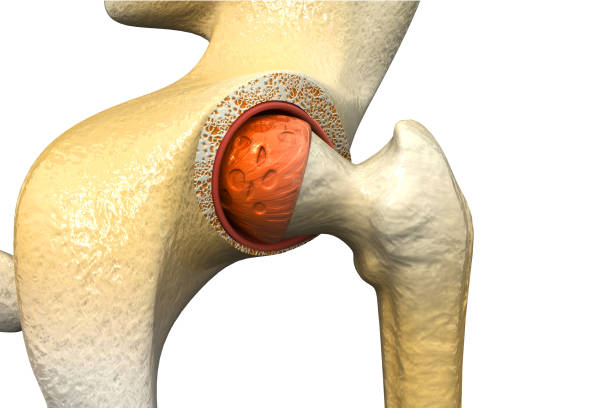

- Avascular Necrosis (AVN):

- It is a condition where blood flow to the femoral head (hip bone) is reduced, causing bone tissue death.

- Symptoms are like gradual onset of pain, limping, limited range of motion.

- Causes are long-term steroid use, alcohol abuse, trauma, or certain diseases.

- AVN can collapse the hip joint if not treated early—often requiring surgery or joint replacement.